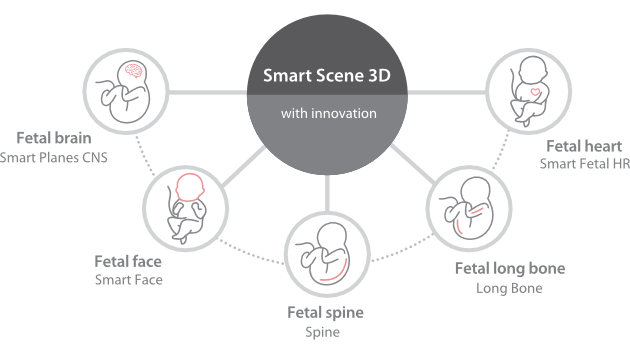

Comprehensive Imaging Solutions Powered by ZST+

The ZST+ platform is an extraordinary innovation, representing an ultrasound evolution. Transforming ultrasound metrics from conventional beam-forming to channel data based processing. It overcomes the traditional trade-off limitation among spatial resolution, temporal resolution and tissue uniformity, delivering exceptional image quality for infinite imaging solutions with non-stop improvements.